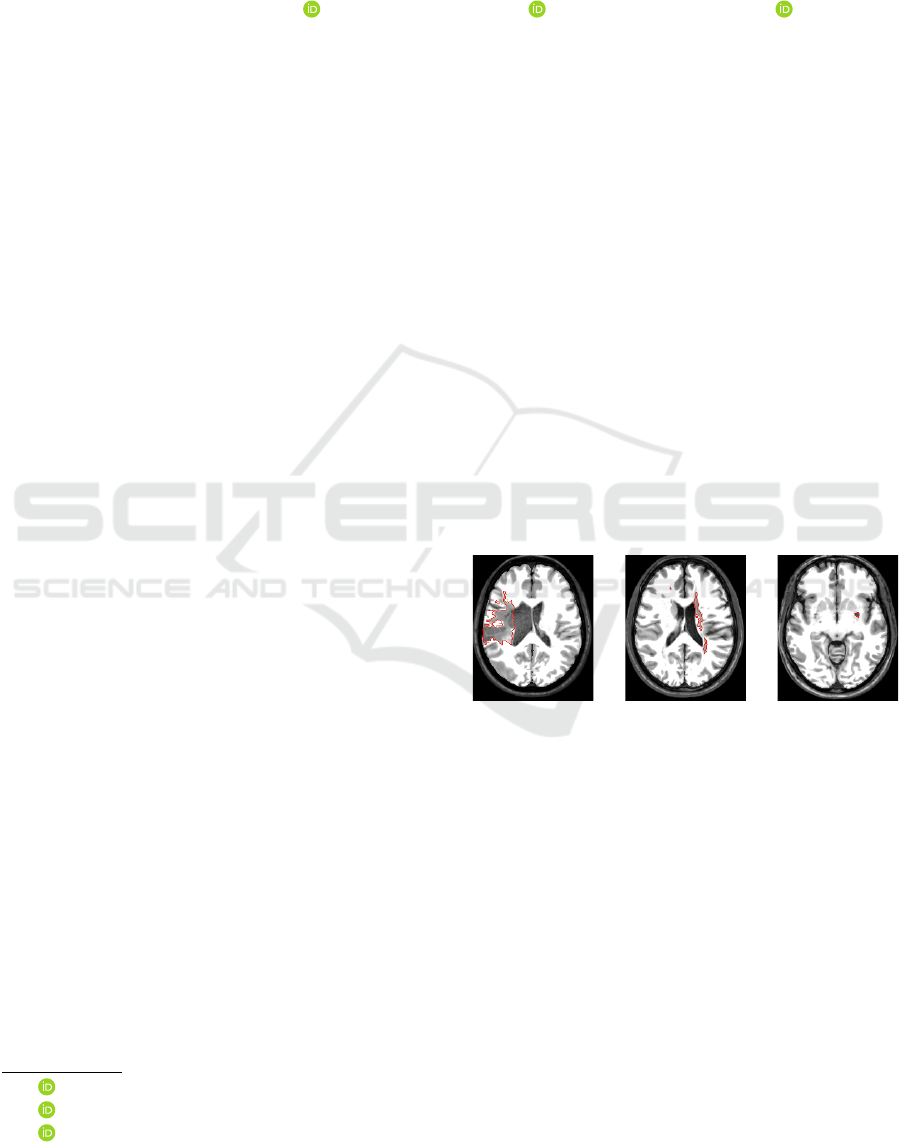

cerebellum and brainstem (detection rate of 0.6829).

Indeed, some lesions seems to be more challenging,

specially in the cerebellum, whose appearances are

similar to their surrounding tissues (Fig. 6, Image

6). However, its FP scores are similar to those of

hemispheric lesions which confirms the stability of

the method (compare rows 2-4 for BADRESC in Ta-

ble 1).